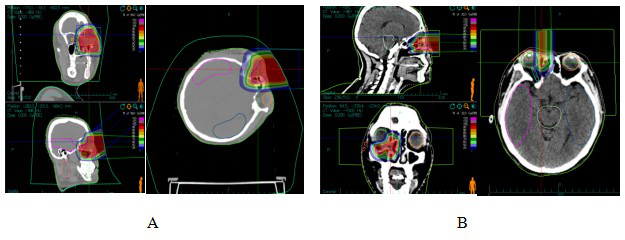

1、临床资料

病例1:女性,44岁,右侧泪囊鳞癌。于2022年7月就诊我院,查体见右眼下眼睑大小约3cm×4cm肿物,眼球运动各方向轻度受限。经过对患者全面检查和评估,患者于2022年7月20日接受CIRT治疗。一程处方剂量:PTV 40Gy(RBE)/10fx;侧卧位,2D均匀扫描,剂量分布见图1A。二程处方剂量:PTVboost 24Gy(RBE)/6fx;仰卧位,2D均匀扫描。肿瘤区总剂量为 64 Gy (RBE)/16 F,4.0 Gy (RBE) /F,5 F/w,剂量分布见图1B。CIRT和容积调强放射治疗(VMAT)计划在均满足处方要求的前提下,轴位图像剂量分布的对比,周围正常组织CIRT计划较VMAT计划低剂量照射范围明显缩小,见图2A和图2B。CIRT治疗前、后通过影像学资料对比疗效,根据实体瘤疗效评价标准(RECIST)1.1评估患者疗效,治疗后3个月,疗效达完全缓解(CR),见图3。CIRT治疗期间及治疗后1月内,患者出现1级急性放射性结膜损伤;于放疗结束3个月后出现眼干,长期使用滴眼液,考虑为1级放射性结膜损伤(RTOG急性放射损伤分级),未观察到大于2级的晚期不良反应。CIRT治疗期间联合使用靶向(西妥昔单抗),治疗期间出现面部散发皮疹,不良事件通用术语评价标准1级。截至2024年9月,目前患者无病状态,继续长期随访。

图1泪囊鳞癌CIRT治疗剂量分布图

Figure 1 CIRT dose distribution in patients with dacryocystosquamous cell carcinoma

Note: Figure 1A: One course CIRT dose distribution. Figure 1B: Two course CIRT dose distribution

图2 泪囊鳞癌患者VMAT计划及碳离子计划剂量分布图

Figure 2 VMAT plan and carbon ion plan dose distribution in patients with dacryocystosquamous cell carcinoma

Note: Figure 2A: VMAT plan dose distribution in patients with dacryocystosquamous cell carcinoma. Figure 2B: Carbon ion plan dose distribution in patients with dacryocystosquamous cell carcinoma.